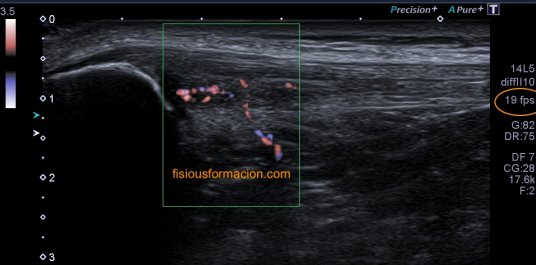

Una vez que tuve controlado el aspecto normal de músculo en la misma localización donde la paciente tenía el bulto, me dirigí a la región del bultoma y estudié la lesión, descrita con anterioridad, siguiendo el protocolo de actuación en caso de neoformaciones, control, medidas, doppler color y power y finalmente comparativa.

El estudio doppler arroja el hallazgo de un vaso importante que está alcanzando y nutriendo la región afectada. Puedes observar como es un vaso de alto flujo y de buen tamaño. No pude demostrar vascularización perimetral de la lesión.